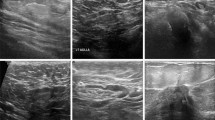

Breast cancer, a widespread global disease, represents a significant threat to women’s health and lives. Many researchers have proposed computer-aided diagnosis systems for classifying breast cancer. The majority of the approaches primarily utilize deep learning methods, which overlook the crucial necessity of incorporating both local information for precise tumor detection. In addition, available breast cancer datasets are imbalanced in nature. Therefore, this paper presents the hybrid breast network (HBNet) for detection of breast cancer, designed to address two critical challenges: class imbalance and incorporation of both global and local information in achieving precise tumor classification. To overcome the problem of class imbalance, HBNet incorporates the borderline synthetic minority oversampling technique. Simultaneously, it employs a feature fusion approach to combine deep and handcrafted features extracted by utilizing ResNet50 and HOG which incorporates global and local information. Moreover, the proposed method integrates the block-matching and 3D denoising filter to effectively eliminate multiplicative noise that has enhanced the performance of the system. The proposed HBNet is evaluated with BUSI and UDIAT datasets and achieved an average accuracy of 95.824% and 90.37%, respectively.

UDIAT (2017). http://www2.docm.mmu.ac.uk/STAFF/m.yap/dataset.php)

Al-Dhabyani W, Gomaa M, Khaled H, Fahmy A (2020) Dataset of breast ultrasound images. Data Brief 28:104863